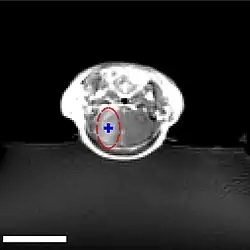

Sur le modèle animal de la souris, on a utilisé des ultrasons focalisés dans le domaine de 0,5 à 2 MHz[139], avec de brèves impulsions de l'ordre de la milliseconde, répétées à intervalles de 1 s, pour une durée totale inférieure à une minute[140]. La fréquence optimale se situe au-dessous de 1 MHz[141]. La puissance acoustique instantanée est inférieure au watt, et donc la puissance moyenne de l'ordre du mW. Les microbulles utilisées sont en général des microbulles autorisées pour l'échocardiographie de contraste. Elles ont typiquement un diamètre de 3 à 5,5 μm, et sont composées typiquement d'albumine humaine, remplie d'octafluoropropane ou de gaz lourd semblable[142].

Les ultrasons peuvent être focalisés sur n'importe quel domaine du cerveau. C'est ainsi que l'on peut ouvrir la barrière hémato-encéphalique sélectivement sur des régions délimitées du cerveau. Les médicaments administrés pénétreront alors sur la zone ainsi ciblée[138]. On peut suivre le ciblage des zones par une IRM simultanée : il suffit d'administrer un produit de contraste IRM, comme du gadolinium convenablement chélaté, qui pénètre dans le cerveau à travers les parties de la barrière hémato-encéphalique ouvertes. Ces parties deviennent alors visibles en IRM. Les produits de contraste ne sont pas en mesure de franchir la barrière aux endroits où elle n'est pas ouverte.